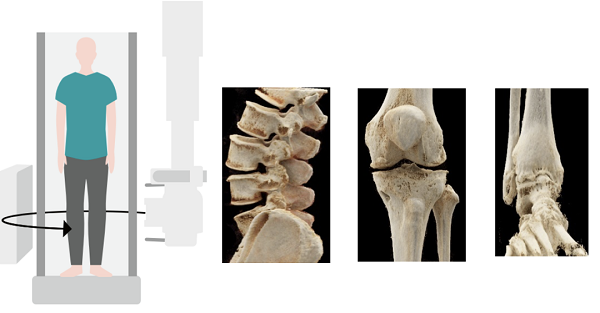

根据西门子Multitom-Rax装机医院使用反馈来看,Multitom-Rax主要价值是其具备的立位3D扫描技术。Multitom-Rax悬吊动态DR,能够完成200°的广角扫描,同时具备高DQE和低剂量的技术特点。在三维影像的清晰度处理上,Multitom-Rax悬吊动态DR可以完成0.25mm空间分辨率影像重建,支持包括全CT功能分析,包括:MPR多平面重建技术、MIP密度投影重建技术和VRT(3D)技术,在三维影像重建技术上与CT无异,支持MAR金属伪影去除。在立位下可以对相关腰椎疾病、膝关节疾病以及踝关节疾病,进行更加精准的评估分析。这也是锥形束断层摄影检查系统之所以价格昂贵的重要原因,基于站立位下的脊柱关节三维成像,在临床疾病评估、治疗方案规划以及治疗后病情进展评估,具有重要的临床价值。

由于人体骨骼在承重与非承重状态下所承受的压力不同,关节间隙的差异在站卧之间可达数倍。CBCT平板和球管围绕患者进行等中心旋转,可实现任意体位的锥形束CT扫描,在脊柱、关节、骨骼获取传统CT检查无法企及的承重位三维图像,真实反映骨骼受力情况并找到病症根源。它引领了立位3D检查的最新方向,精确地对关节力线进行评估,是外科手术成功与远期效果评估的重要因素。

可以说,西门子医疗Multitom Rax创造了立位3D检查的新纪元。它是第一台可以在人自然站立状态下,获得承重位的颈椎、腰椎、膝关节、踝关节的真实三维图像的锥形束CT。通过承重位呈现出的三维图像,它能够真实反映患者畸变部位的严重程度并找到疼痛根源,借助前所未有的诊疗新模式,为临床提供见所未见的站立位新视角。